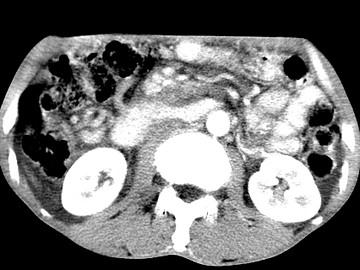

问题 女,50岁,中上腹疼痛,消瘦乏力,影像检查如下图,最佳的诊断是 ( )

选项 A、胰岛素瘤 B、腹膜后淋巴瘤 C、急性胰腺炎 D、胰腺癌并腹膜后淋巴结转移 E、慢性胰腺炎

答案 D